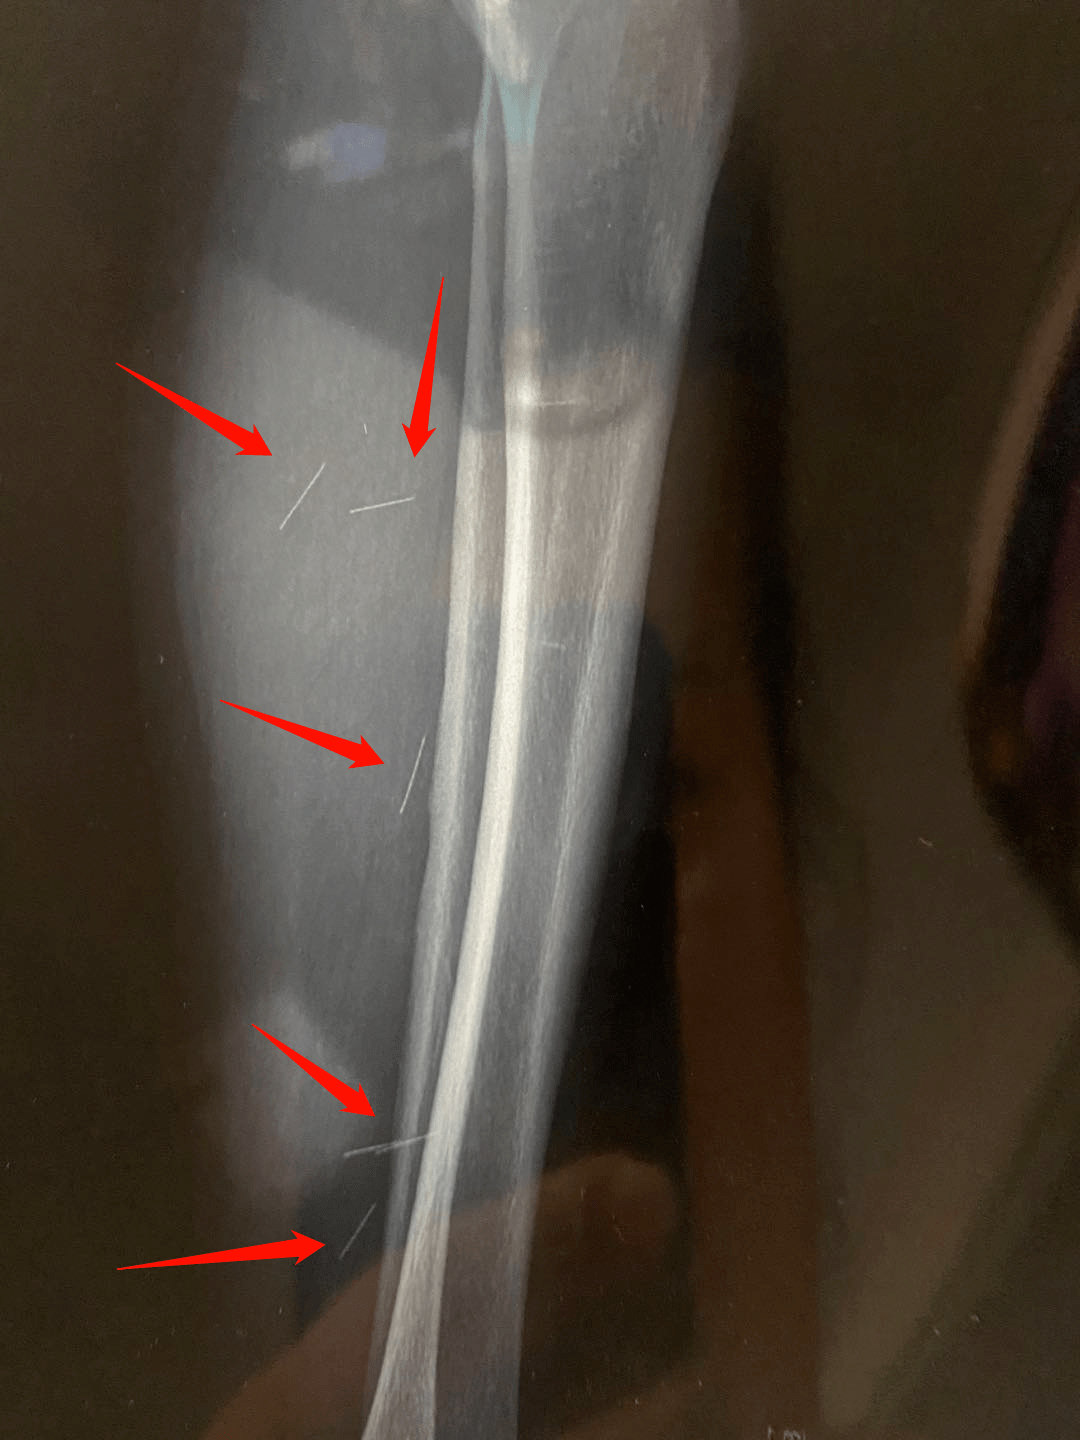

瘆人济南一市民小区诊所针灸后腿里竟发现6根断针诊所回应

图片尺寸1080x1440

6根断针在腿里济南女子针灸后要开刀诊所没有过失

图片尺寸640x406